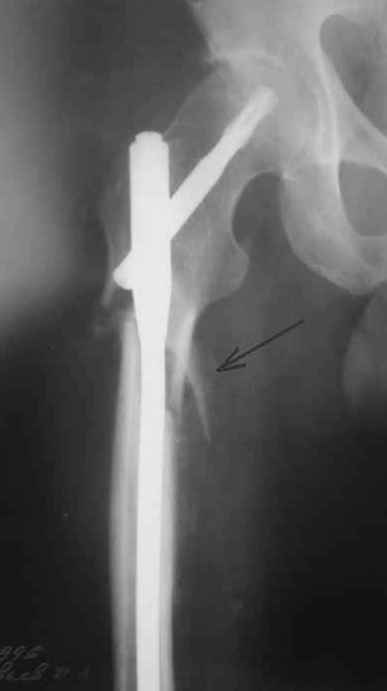

по поводу бедра - все сделано правильно, есть прекрасная апозиция основных фрагментов почти на всем диаметре перелома, в этом районе прекрасное кровоснабжение и нет никакого смысла гончяться за осколком

небольшое замечание по поводу бедра - сразу не рассмотрел - гвоздь обязательно надо было заблокировать дистально и крайне желательно -и проксимально тоже. Без блокирования не исключена ( хоть и не очень вероятна) ротация фрагментов.

Практически единственное, что делает необходимым разрез для манипуляций с промежуточным отломком бедренной кости - это его "застегивание" в илиотибиальном тракте по типу пуговицы в петле.

Когда при движениях в колене этот отломок на сантиметры смещается, создавая очевидный дискомфорт. Даже в этом случае репозиция отломка

именно в его ложе избыточна, достаточно осциллирующей пилой отсечь то, что выстоит над фасцией.

Отломок, расположенный так, как на показанных рентгенограммах бедра, обычно на снимках в 1-2 мес. уже располагается ближе к диафизу и

включается в мозоль.

На операции я оставил осколок в области приводящих мышц бедра (ни пальпаторно, ни спицей сдвинуть не смог, "заклинило" насмерть). Фото спустя 2 месяца после операции (PFN).

Только сейчас пациент стал более или менее активным. Сразу после операции жалобы на сильные боли при отведении и приведении бедра в области отломка. Сейчас отломок пальпируется и пациент испытывает дискомфорт, хотя амплитуда движений объективно прогрессирует.

Теперь думаю, надо все-таки было через минидоступ или резецировать, либо репонировать. Обычно при таких операциях уже на 2-й день пациенты на костыли и по отделению, а у этого задержка длительная получилась. Только спустя 2 недели кое-как на костыли взобрался. Ни отека, никакой неврологии, только эти боли в области осколка.